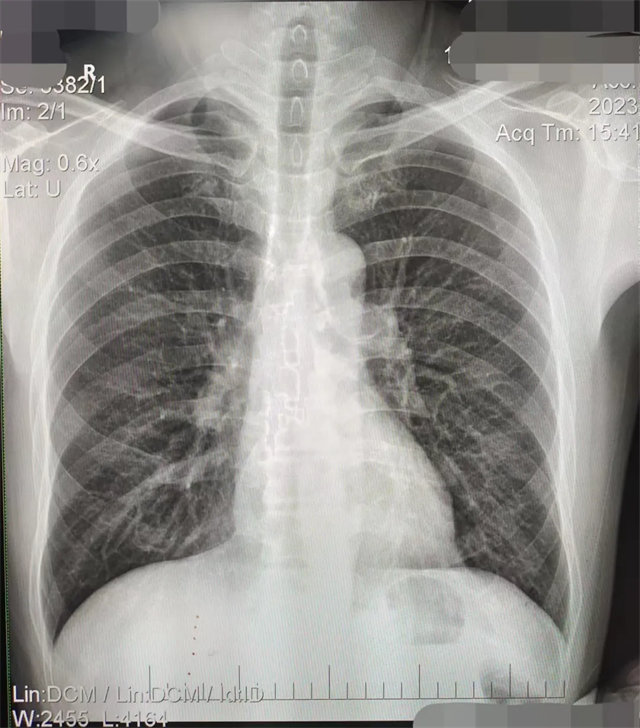

缺陷:兩肩胛骨未拉開肺野之外,吸氣不完全,且存在金屬飾品遮擋。

解決:去除金屬飾品及內(nèi)衣后重新按標準體位攝片即可。